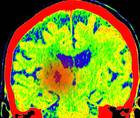

09/09/2024- Medical NewsHuman Brain Cancers Fire Electrical Impulses: Researchers Reveal Unexpected Hybrid Cell Spiking the Signals